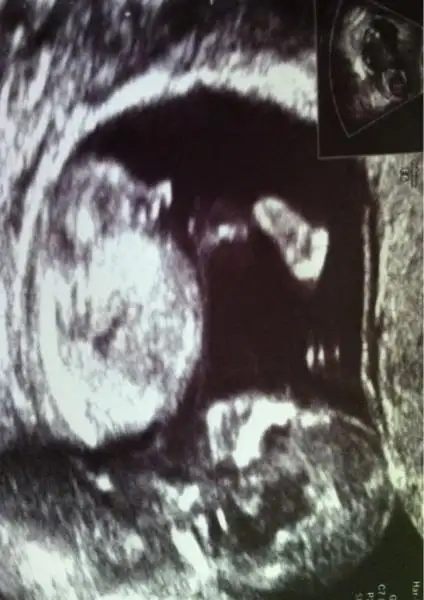

dr soylemeden siz gorun genital nub teorisi ( bebegin cinsiyeti)

merve birde neresi benziyor "nub" neresi oluyor?

Ben sadce tahmin istiyorm ben burayi cok takip ettim .. biliyorum tipinden ense kalinligi diyolar nubdan ne bilim sadece tahmin istiyorm ikinci cocugum ama cok merak ediyorum off kafayi yicem hele bide doktor masalahh dedi bi tahminde bulunuyrm ama umutlandirmak istemiyrm dedim bununda cok etkisinde kaldim kiz cocuklari gec gelisiyomus erkek cocu ise erken kim gorse erkek dio bilmiyrrm tabikide hayirlisini istiyorum allahmdan

Bende rahatlamistim tabi erkrkde olsa hayirlisi olsun da peki nubu zaten ortada dglmi anlasiliyo yani .bide sunu sorcam nubun dogruluk payi yuzde kac canimm

teyzeleri Allah rizasi icin bi bakin, bizim bebisin cinsiyetini tahmin edebilicek olan varmi ? bu arada masAllah demeyi unutmayin benim kuzuma